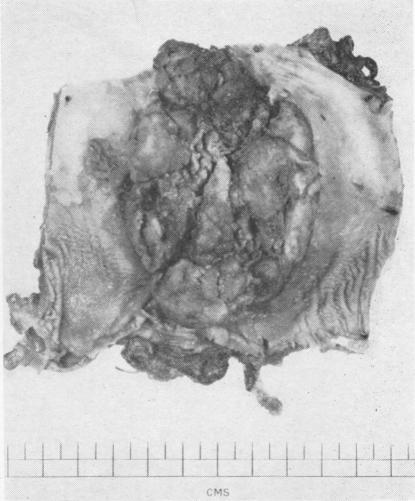

SMITHERS D W

Thorax. 1956 Dec;11(4):257-67. doi: 10.1136/thx.11.4.257.